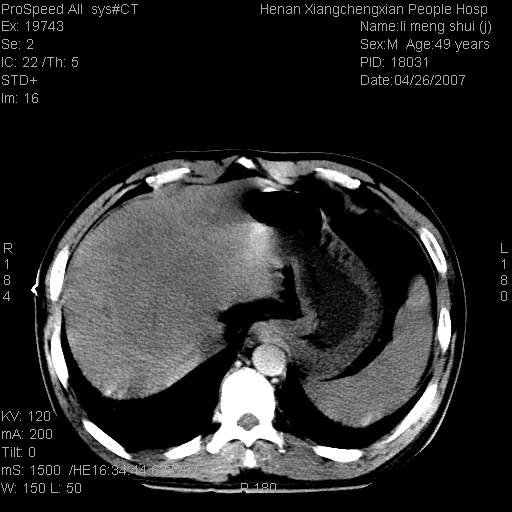

| 患者,男,49岁, 腹疼伴恶心\\呕吐20天,20天前无明显诱因出现右上腹部疼痛,钝疼,无放射,伴恶心\\呕吐,不伴发热.患者不愿增强. b超:肝脏右叶实性占位. ct:肝脏右叶可见一巨块状圆形低密度影,大小约93mm*84mm,其内可见点状高密度影,胆囊、胰腺、脾脏大小、形态及密度未见异常,腹膜后间隙未见肿大淋巴结影。 印象:肝脏右叶巨大肿块,性质待定,建议增强并穿刺活检进一步确诊。 ct平扫: ![]() ![]() ![]() ![]() ![]() ![]() ![]() ![]() ![]() ![]() ![]() ![]() ![]() ![]() ![]() ![]() ![]() 肝脏右叶肿块ct引导下穿刺活检术 患者于16时05分仰卧于ct检查台上,首先行肝脏ct扫描确定进针位置、深度、角度。在局麻下行ct引导下肝脏右叶肿块穿刺活检术。常规消毒、铺巾、局麻。在ct引导下使活检针经右侧腋中线、第9肋间隙垂直胸壁进针90mm,针头进入病变预定位置。在病变预定位置多点、多方向抽取小米样病变组织多块,涂片五张送病理检查。术后穿刺点局部无出血,未出现腹腔积液等并发症。术中及术后患者生命体征稳定,手术于17时10分成功完成。患者安返病房。 穿刺片 ![]() ![]() ![]() ![]() ![]() ![]() ![]() ![]() ![]() ![]() ![]() ![]() ![]() ![]() ![]() ![]() 病理结果肝细胞癌 ![]() 原贴地址:http://www.radinet.com.cn/forum_view.asp?forum_id=4&view_id=24130 ok |